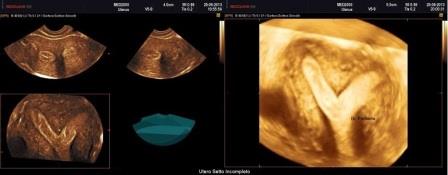

Utero Bicorne

L'utero bicorne è conseguenza della mancata o incompleta fusione dei dotti di Muller e rappresenta circa il 10% di tutte le anomalie mulleriane. E' caratterizzato dalla presenza di due distinti corni uterini divergenti che si fondono verso il fondo dell'utero o a livello del segmento uterino inferiore o a livello dell'istmo ( utero bicorne unicolle).

Dal punto di vista ecografico si osserva una divergenza degli echi endometriali, meglio evidente alla elaborazione 3D. Importante la diagnosi differenziale con l'utero setto (nell'utero bicorne si ha una incisura del fondo uterino maggiore di 10 mm.) e con l'utero didelfo (nell'utero bicorne i due corpi sono separati tra di loro da un angolo superiore a 60°).

Se si associa la presenza di una vagina atresica o di setti vaginali (25% dei casi) possono associarsi anomalie dell'apparato urinario (agenesia renale, rene ipotrofico, ectopia renale).

L'utero bicorne non è causa di infertilità ma sono più frequenti gli aborti spontanei nel I trimestre e soprattutto il parto pretermine, perchè le due cavità uterine sono più piccole.

E' importante sottolineare che anche l'utero bicorne non è incompatibile con il completamento di una gravidanza fisiologica.